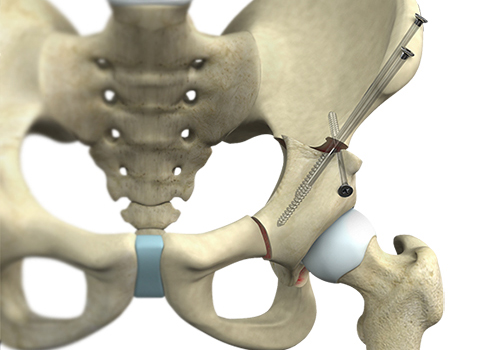

Anterior hip replacement is a minimally invasive hip surgery performed to replace the hip joint without cutting through any major muscles. It is also referred to as muscle-sparing surgery because no major muscles are cut enabling a quicker return to normal activity.

Hip replacement surgery is one of the most common orthopedic surgeries performed. It involves the replacement of the damaged hip bone (ball shaped upper end of the femur) with a ceramic ball attached to a metal stem that is fixed into the femur and placing a new cup with a special liner in the pelvis.

Revision hip replacement is a complex surgical procedure in which all or part of a previously implanted hip joint is replaced with a new artificial hip joint. Total hip replacement surgery is an option to relieve severe arthritis pain that limits your daily activities.